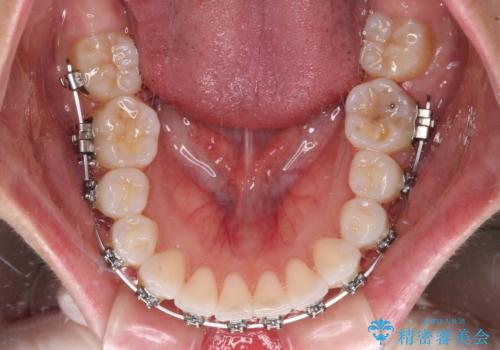

- 矯正装置

- メタルブラケット

奥歯の咬み合わせを維持しながら正中位置を改善するために、補助装置を使用しました。

予定より期間がかかりましたが、上下の正中位置を綺麗に一致させることができました。